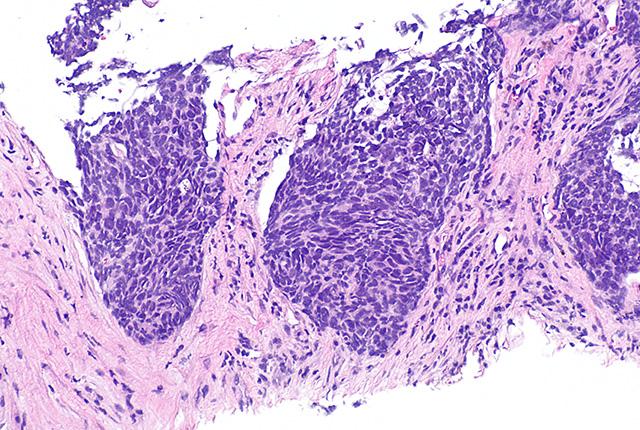

Standard care for stage III non-small cell lung cancer is radiotherapy and concurrent chemotherapy. Even so, approximately 50% of patients experience tumor recurrence within the radiotherapy field. Reducing such “local” recurrences has been shown to enhance survival of these patients, and radiation oncologists are focused on improving radiotherapy’s tumor control.